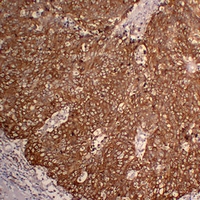

(Immunohistochemical analysis of Cytokeratin 5 staining in human lung squamous cell carcinoma formalin fixed paraffin embedded tissue section. The section was pre-treated using heat mediated antigen retrieval with sodium citrate buffer (pH 6.0). The section was then incubated with the antibody at room temperature and detected using an HRP conjugated compact polymer system. DAB was used as the chromogen. The section was then counterstained with haematoxylin and mounted with DPX.)

(Immunohistochemical analysis of Cytokeratin 5 staining in human squamous cell lung carcinoma formalin fixed paraffin embedded tissue section. The section was pre-treated using heat mediated antigen retrieval with sodium citrate buffer (pH 6.0). The section was then incubated with the antibody at room temperature and detected using an HRP conjugated compact polymer system. DAB was used as the chromogen. The section was then counterstained with haematoxylin and mounted with DPX.)